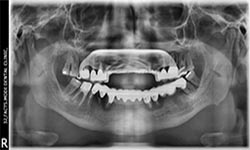

(22)

Before Treatment

OPG (Pre Treatment)

After Areatment

OPG (Post Treatment)

Case of full mouth rehabilitation All teeth extracted Upper single complete denture and lower Implant supported denture